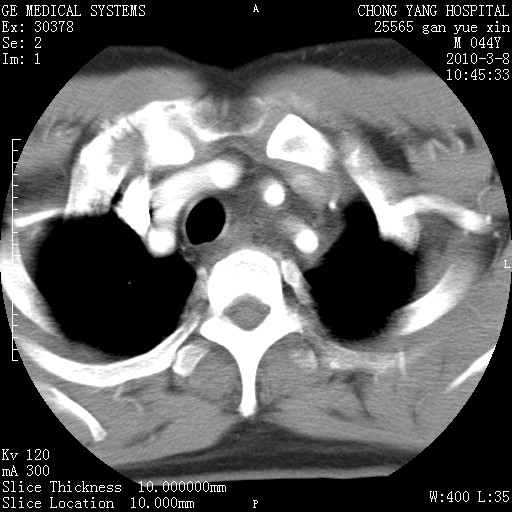

标题: CT24940:主动脉增强,典型病例。 [打印本页]

标题: CT24940:主动脉增强,典型病例。

夹层动脉瘤。

动脉夹层

夹层动脉瘤,典型

主动脉夹层。

动脉夹层的分型:

⒈debakey分型:根据主动脉夹层累及部位,分为三型:ⅰ型:原发破口位于升主动脉或主动脉弓部,夹层累及升主动脉、主动脉弓部、胸主动脉、腹主动脉大部或全部,少数可累及髂动脉。ⅱ型:原发破口位于升主动脉,夹层累及升主动脉,少数可累及部分主动脉弓。ⅲ型:原发破口位于左锁骨下动脉开口远端,根据夹层累及范围又分为ⅲa,ⅲb。ⅲa型:夹层累及胸主动脉。ⅲb型:夹层累及升主动脉、腹主动脉大部或全部。少数可累及髂动脉。

⒉stanford分型:a型:夹层累及升主动脉,无论远端范围如何。b型:夹层累及左锁骨下动脉开口以远的降主动脉。

夹层动脉瘤,少量胸水

夹层动脉瘤;左侧少量胸腔积液。

典型主动脉夹层。